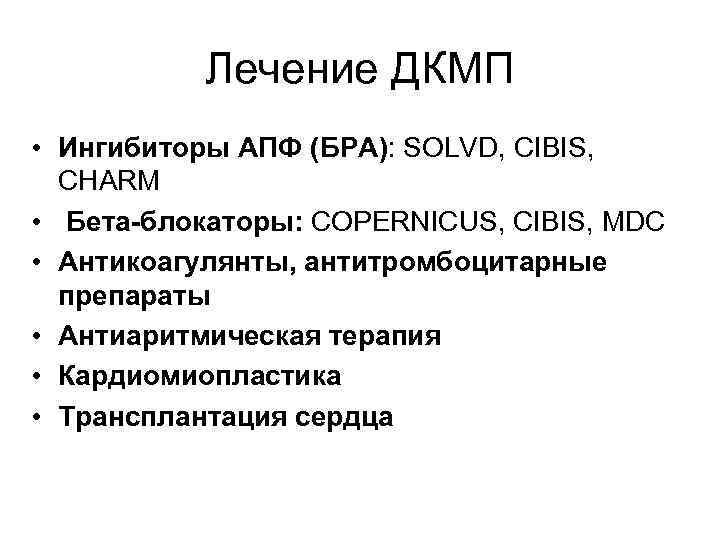

Лечение ДКМП • Ингибиторы АПФ (БРА): SOLVD, CIBIS, CHARM • Бета-блокаторы: COPERNICUS, CIBIS, MDC • Антикоагулянты, антитромбоцитарные препараты • Антиаритмическая терапия • Кардиомиопластика • Трансплантация сердца

Лечение ДКМП • Ингибиторы АПФ (БРА): SOLVD, CIBIS, CHARM • Бета-блокаторы: COPERNICUS, CIBIS, MDC • Антикоагулянты, антитромбоцитарные препараты • Антиаритмическая терапия • Кардиомиопластика • Трансплантация сердца